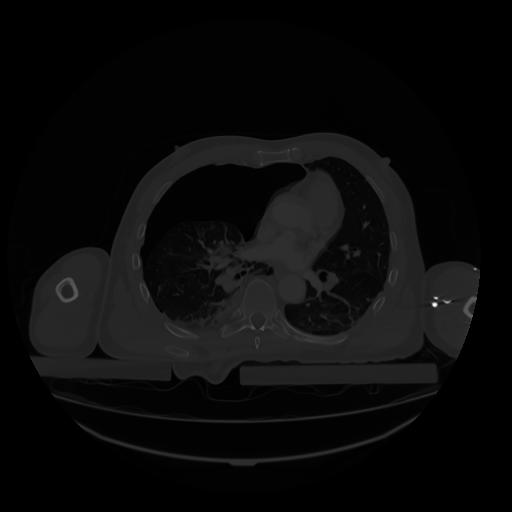

28 CUERPO,CE,Vol,2.0,CUERPO,,